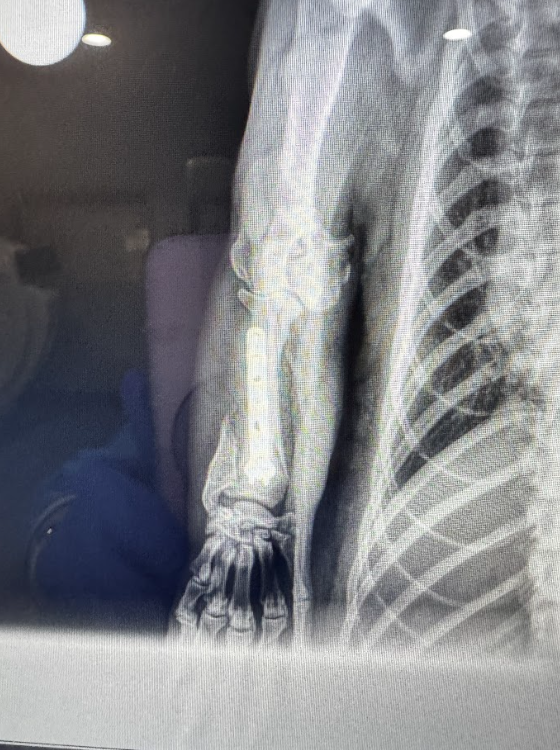

The badger’s intake exam revealed that he had a broken radius and ulna, the two bones in his right foreleg. He also had multiple puncture wounds in his chin, which may have come from his own massive claws if he was tumbled when the vehicle hit him, and a broken tooth.

WildCare’s Veterinarian Dr. Sorem, placed a temporary cast on the badger’s foreleg while the team reached out to veterinary orthopedic specialists around the Bay Area in search of a surgeon who could take on the challenging repair of the broken radius and ulna.

“At Lenity, surgeon Dr. Kayla Caturay and anesthesiologist Dr. Maria Glowaski undertook a grueling 6-hour procedure to repair the fracture. The well-developed musculature of the badger’s forelimbs made alignment of the fracture fragments challenging, but Dr. Caturay persisted and was able to reduce the fractures and secure them in place using a titanium plate. After the hours-long surgery, she closed the surgical incision in three separate layers with no external sutures to reduce the possibility that the badger would open it back up during his badger activities.”